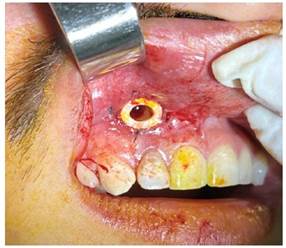

Obteniendo como diagnóstico presuntivo un quiste radicular asociado a la pieza 1.2; se le solicitó al paciente una biometría hemática, con todos los valores dentro de parámetros normales; se realizó el procedimiento quirúrgico de descompresión, por medio de una incisión lineal, el levantamiento del colgajo mucoperiostico y posterior osteotomía a nivel del ápice de la pieza 1.2, hasta descubrir la membrana del quiste (figura 3a), se extiende la ventana con un diámetro de aproximadamente 5 mm compatible con el diámetro del dren que colocaríamos, se realizó una incisión a nivel de la membrana del quiste y se drenó líquido seropurulento, se realiza el lavado mediante el orificio, con suero fisiológico y yodopovidona (Figura 3b).

Figura 3a Se observa ventana de 5 mm de diámetro que se realizó mediante osteotomía a nivel del ápice de la pieza 1.2; observamos la membrana del quiste.

Figura 3b Se retiro la membrana del quiste a nivel de la ventana ósea y se realizó el drenaje del líquido seropurulento, lavamos a través del orificio con suero fisiológico y yodopovidona.